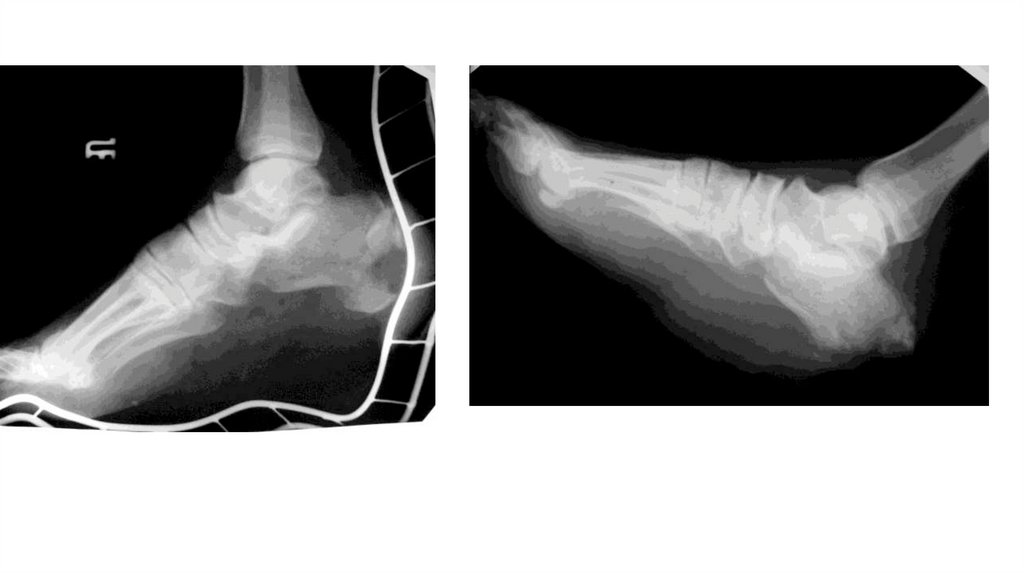

Воспалительные заболевания опорнодвигательного аппарата

«Воспалительные

заболевания опорнодвигательного аппарата»